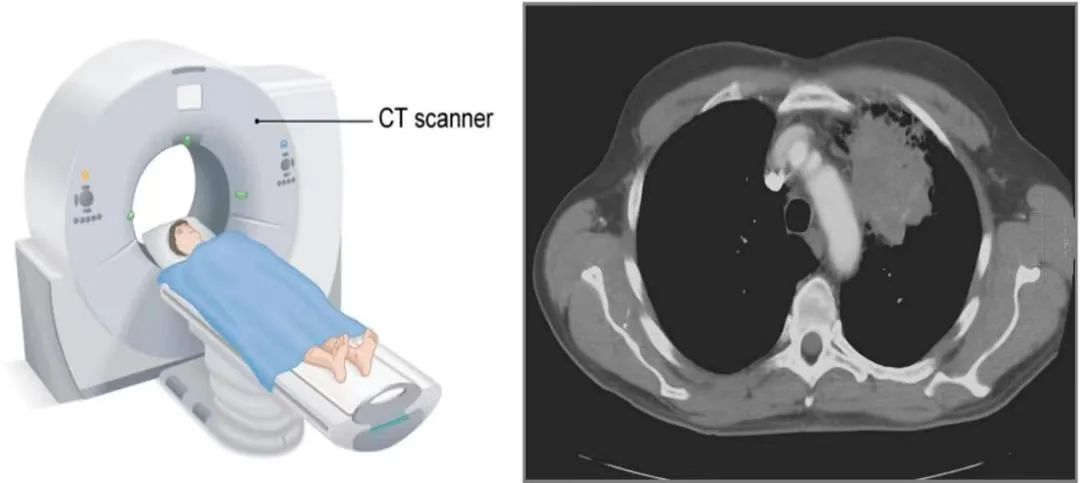

【影像报告解读】双肺多发小结节影:是病吗?要紧吗?该怎么办?

⚠️ 声明:本文为医学科普与健康常识分享,不构成诊疗意见,不能替代医生处方与指导。如有异常结果,请务必遵医嘱或咨询专业医生,切勿自行判断或延误复查。 一、 什么是“双肺多发小结节影”? 当你拿到胸部 CT 报告,上面写着: “双肺可见多发小结节影,大小约 2–5mm,边界清晰 / 模糊不等。